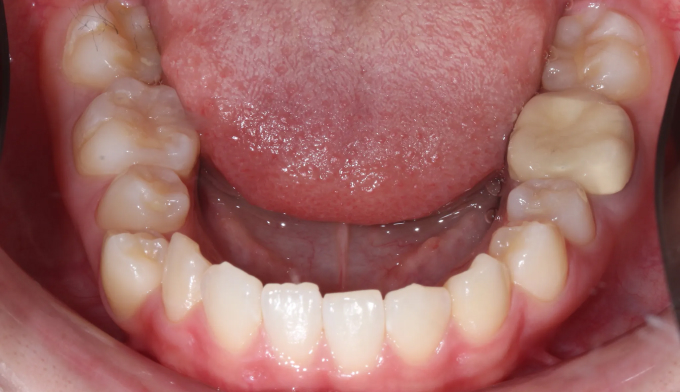

앞니 하나만 뒤로 들어간 경우, 해당 치아만 앞으로 빼내면 되는 간단한 교정이라고 생각하기 쉽습니다.

하지만 해당 치아가 뒤로 들어가면서 전체적인 치열이 한쪽으로 쏠리는 비대칭이 나타났기 때문에 이를 모두 해결하기 위해서는 전체교정을 통한 긴 치료기간이 필요합니다.

안쪽으로 들어간 앞니 양쪽으로 치열을 밀어서 공간을 확보해주고 앞니를 재위치 시켰습니다.

추가로 한쪽으로 틀어진 치열들도 위아래 중심선을 맞추어주었습니다.

총 치료기간은 17개월입니다.